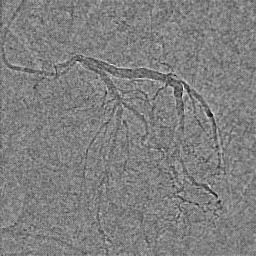

The adoption of machine learning in healthcare calls for model transparency and explainability. In this work, we introduce Signature Activation, a saliency method that generates holistic and class-agnostic explanations for Convolutional Neural Network (CNN) outputs. Our method exploits the fact that certain kinds of medical images, such as angiograms, have clear foreground and background objects. We give theoretical explanation to justify our methods. We show the potential use of our method in clinical settings through evaluating its efficacy for aiding the detection of lesions in coronary angiograms.